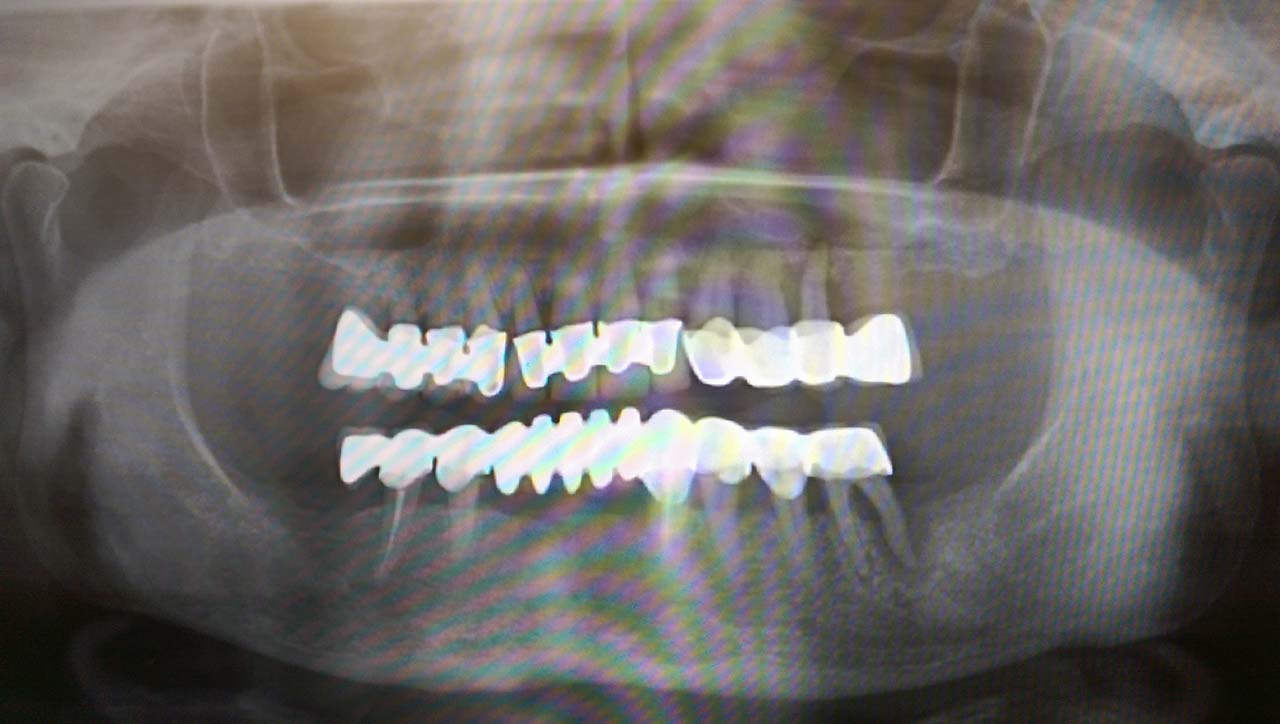

Teljes fogatlanság helyreállítása 2 nap alatt azonnal terhelhető svájci IHDE implantátumokkal és PMMA műanyag hidakkal. Intraorális szkennerrel vettünk lenyomatot az implantáció után, és erre a digitális mintára készítette el a fogtechnika a hidak digitális tervezését, majd faragta ki műanyagból. Ezt a gyors munkát az azonnal terhelhető implantátumok és a digitális lenyomat, tervezés segítségével tudtuk megcsinálni mindössze 2 nap alatt. Dr. Kelemen Péter és a Symbion Fogtechnika munkája.